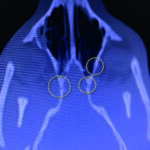

CT scan of skull is preferred for evaluate bone fractures and identify areas of acute hemorrhage or edema. CT scan showed multiple sites of skull fractures, right maxilla, both frontal, right zygomatic, right caudal mandible, right caudal zygomatic, right temporal, left occipital bone (Figure 3) and patchy small area of hyper-attenuation at the cranial of midbrain in pre-contrast study (Figure 4), no detectable mass effect, hypo-attenuated of large edematous parenchyma in the brain, right temporomandibular joint is displacement (Figure 5) and left tympanic bulla shows partial ventral fluid-filled.

Figures 3.1, 3.2, 3.3, 3.4, 3.5, 3.6, 3.7

Figures show multiple sites of skull fractures, right maxilla, both frontal, right zygomatic, right caudal mandible, right caudal zygomatic, right temporal, left occipital bone.